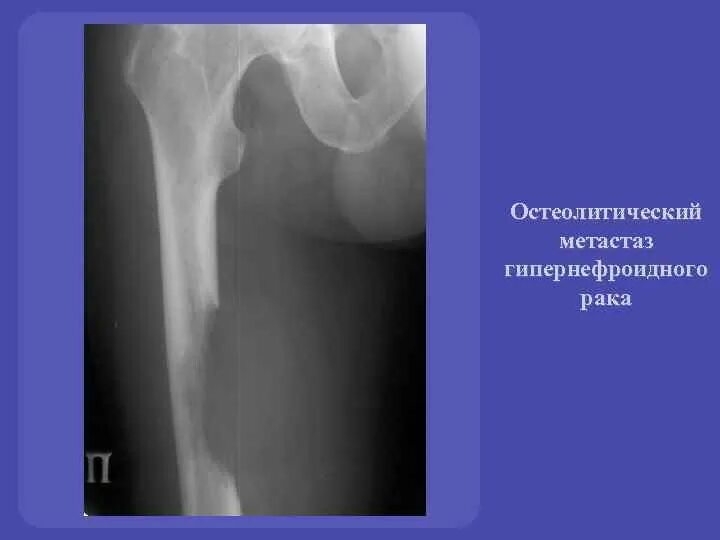

Метастазы в костях при раке предстательной железы